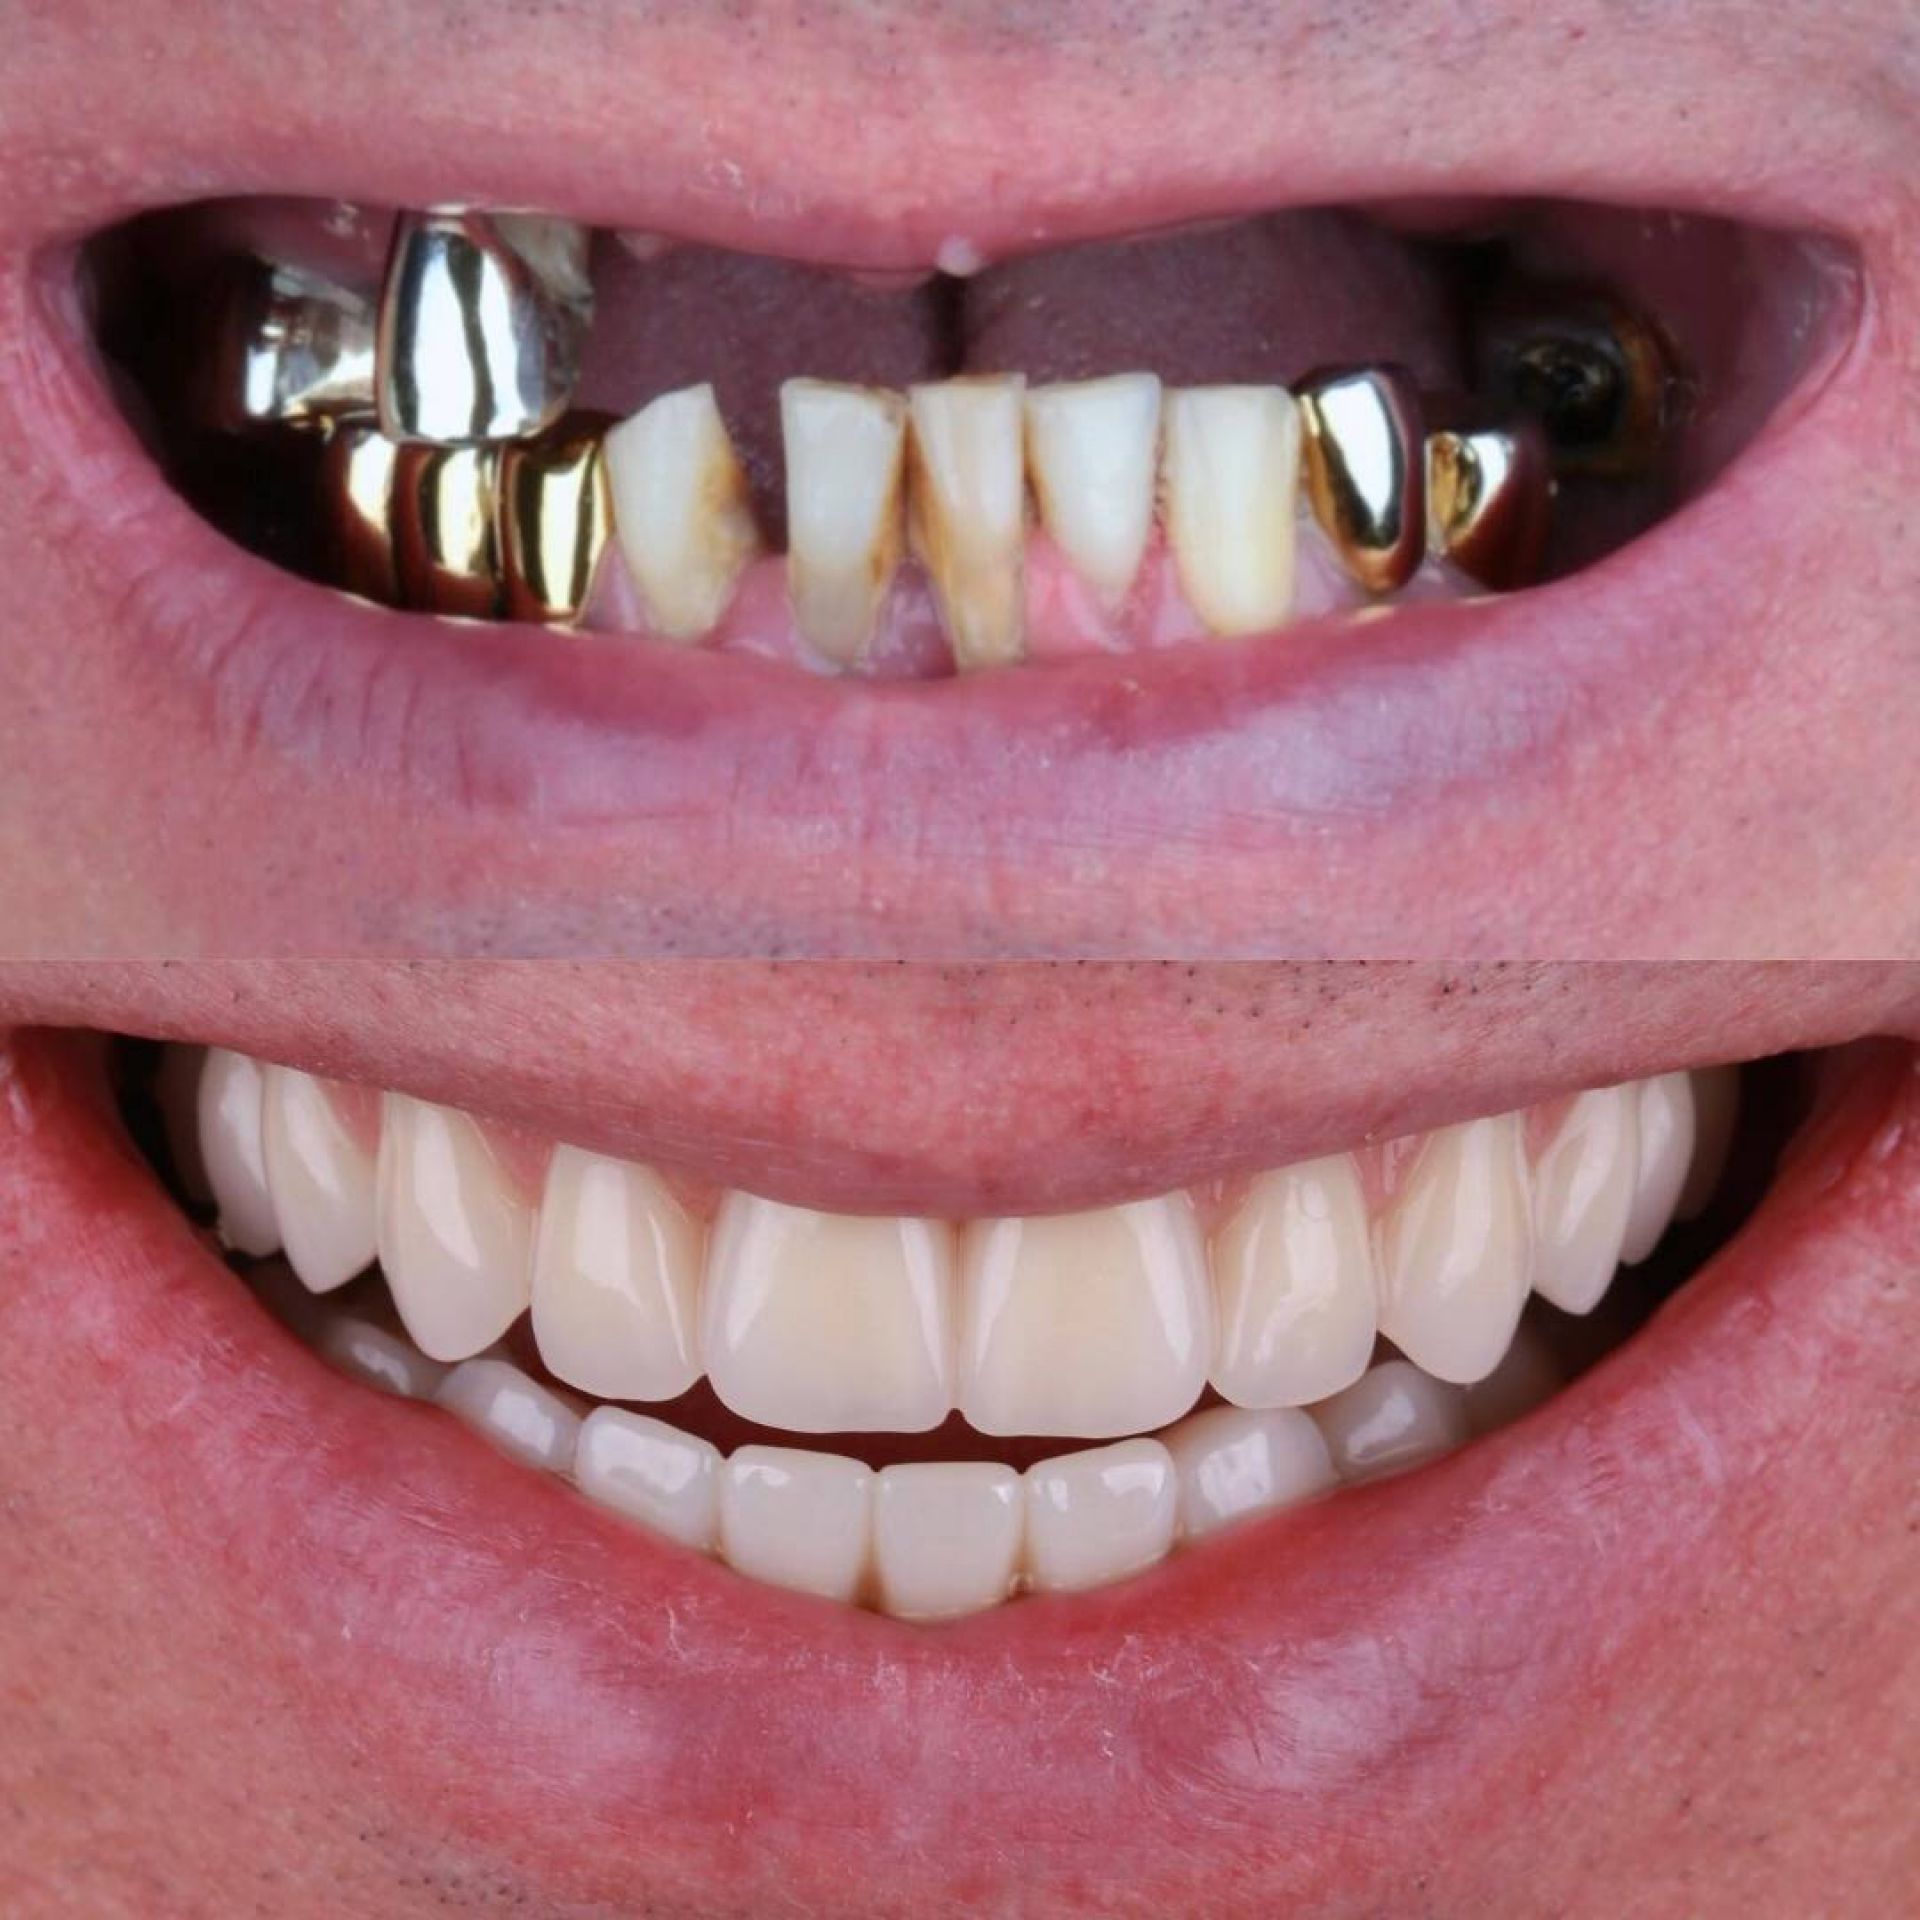

- відновлювати весь зубний ряд завдяки протоколам «all-on-4», «all-on-6», найкращий варіант при повній втраті зубів;

Зубні імпланти - це штучні корінці зубів, які встановлюються в кістку щелепи з метою заміни втрачених зубів.

Імплантація рекомендується в різних випадках втрати зубів:

- Втрата одного або кількох зубів;

- Неможливість носити протези або мостики;

- Покращення функціональності та зовнішнього вигляду;

- Збереження кістки щелепи.

Імплантати мають кілька переваг порівняно з іншими методами заміни втрачених зубів:

- Натуральний вигляд і відчуття

- Довготривале використання